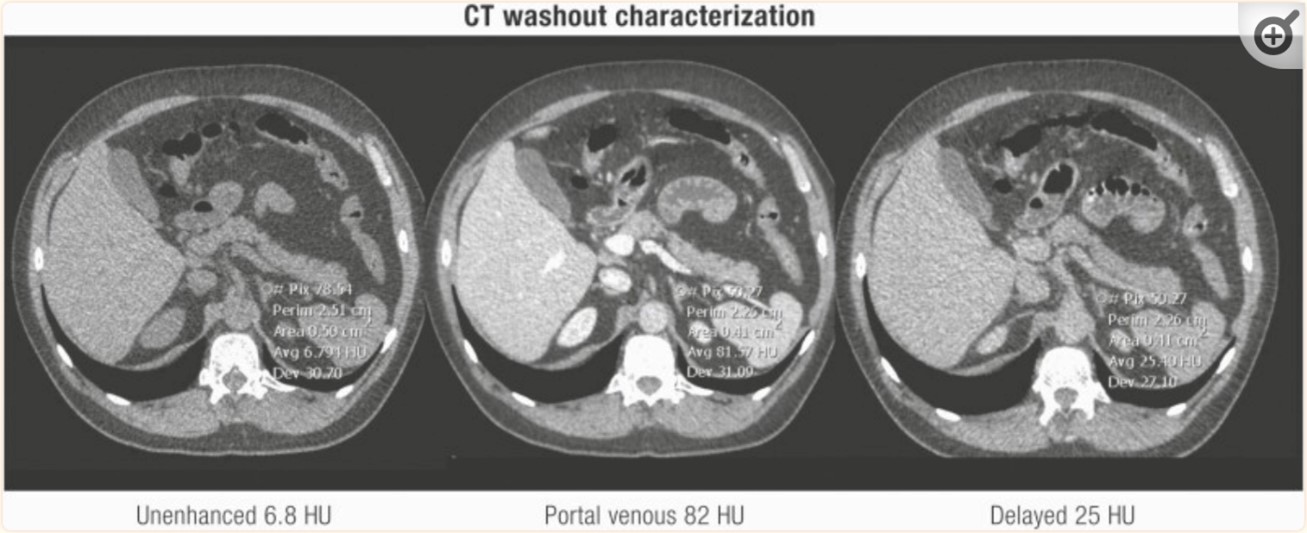

Los estudios de lavado consisten en imágenes de TC realizadas antes y en dos puntos de tiempo después de la administración de contraste intravenoso (normalmente, las imágenes se realizan a los 60-90 segundos y 10 o 15 minutos después del contraste) sin evidencia clara sobre el mejor intervalo de tiempo para el último punto de tiempo.(17) Los adenomas por lo general contrastan rápidamente y muestran un lavado rápido del contraste intravenoso, a diferencia d las lesiones suprarrenales malignas, que por lo general contrastan rápidamente pero demuestran un lavado más lento del medio de contraste.

Valores absolutos de lavado de >60% se obtienen con la siguiente fórmula: (UH contraste temprano – UH contraste retardado)/( UH contraste temprano – UH sin contraste) × 100% sugieren un adenoma benigno.(14,18)

El lavado relativo se puede calcular cuando la TC sin contraste no está disponible (UH contraste temprano – UH retardada)/ UH contraste temprano × 100%.

Los valores de > 40 % sugieren un adenoma benigno.(15,18,19)